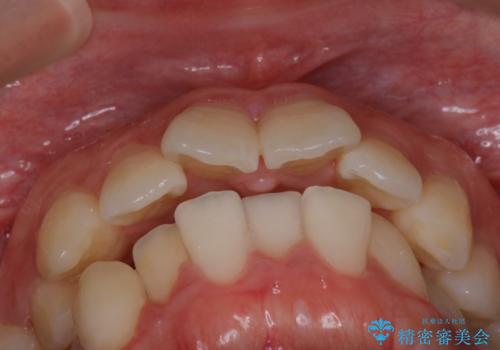

【抜歯インビザ】凸凹を綺麗になおしたい

- 前歯の凸凹を主訴に来院されました。

叢生量が多いため、抜歯が必要となるため、ワイヤー矯正をお勧めしましたが、患者さんの希望によりインビザラインで治療を開始しました。途中でワイヤーリカバリーを必要とせず終了でき患者さんには満足していただけました。